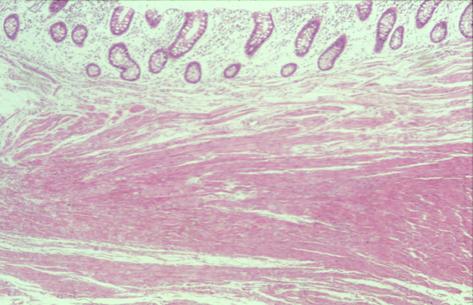

疾病(病理主体)的分类炎症性・溃疡性疾患/结核

部位(按器官分)大肠/占据大肠的2个以上区域

检查方法病理切片(微观)